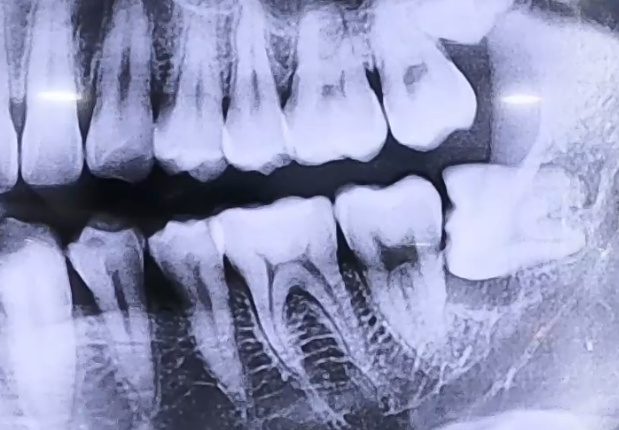

매복 사랑니 치료 사례

AFTER

사랑니로 인한 극심한 통증으로 내원해 주신 환자분입니다.

검사를 진행해 보니 매복 사랑니를 갖고 계셨고, 이 사랑니 아래쪽으로

잇몸에 염증이 생겨 잇몸뼈들이 녹아내리고 있었는데요.

해당 부위의 잇몸이 전반적으로 약해져 있었기 때문에

사랑니 발치 후 그 앞쪽 어금니들의 상태도 주의깊게 살펴야 했습니다.

다행히도 어금니는 많이 흔들리지는 않는 상황이었으므로 사랑니를 발치하고,

약해진 잇몸뼈가 회복될 수 있도록 한 뒤 뼈의 높이를 올리고 보강해 주기 위한

뼈이식 치료를 함께 진행해 드렸습니다.